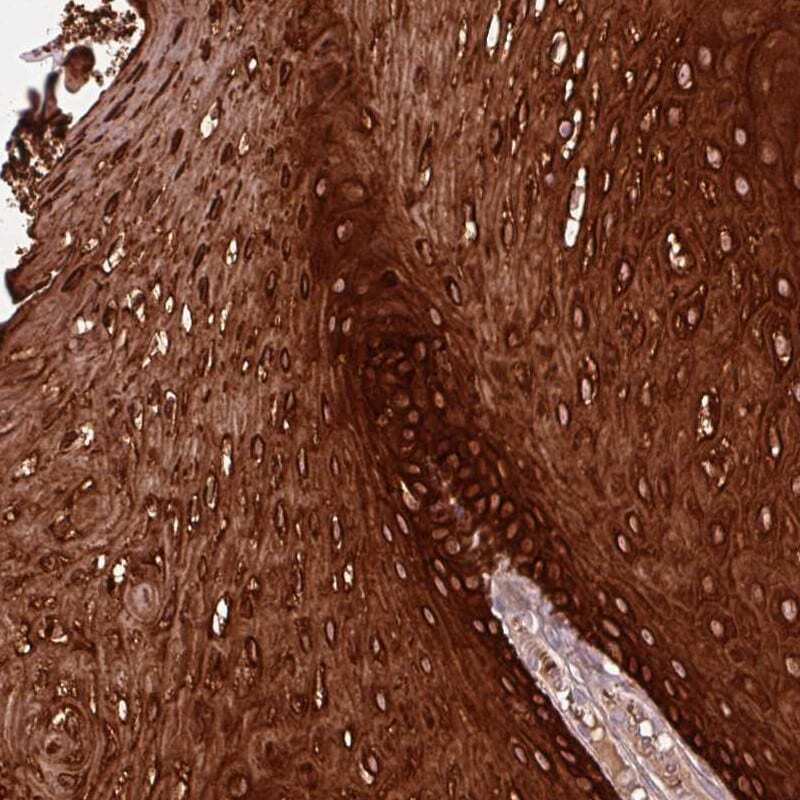

Supportive validation

- Submitted by

- Invitrogen Antibodies (provider)

- Main image

- Experimental details

- Immunohistochemical analysis of ZNF286B in human oral mucosa using ZNF286B Polyclonal Antibody (Product # PA5-64363) shows strong cytoplasmic and nuclear positivity in squamous epithelial cells.